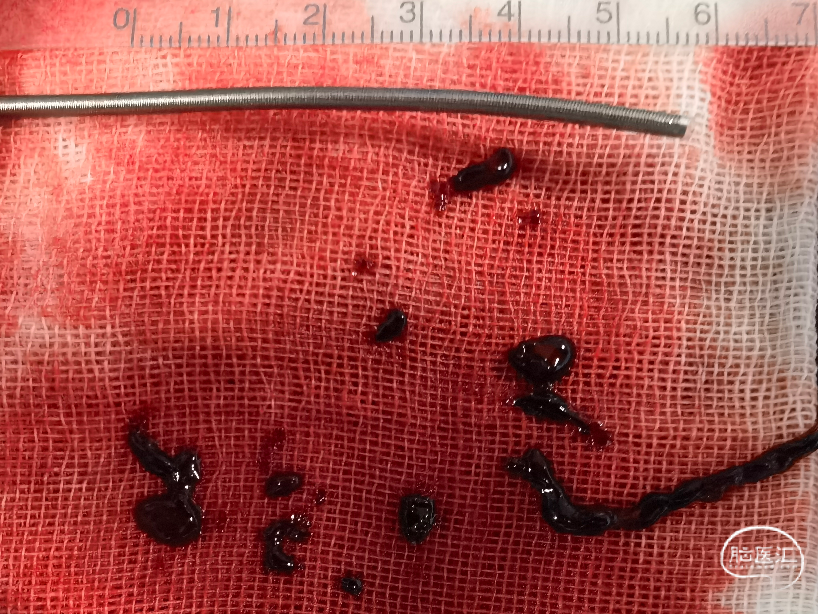

随后选择Sterling3×30 8atm的球囊通过血管进行球囊扩张。选用中间导管进行抽吸,再通过微导管、微导丝进入大脑中动脉,进行持续抽吸,抽吸出长节段血栓。随后近端可见充盈缺损,将保护伞回收,回收血栓后重新植入保护伞。随后进行球囊扩张及支架成型。

2. 血栓性质:可能为红细胞含量较高的血栓。头颅CT影像大脑中动脉走行区高密度征。

栓塞性病变更适合抽吸取栓

血栓性质倾向于红色血栓或混合血栓

抽吸取栓成功率高,血栓逃逸风险小